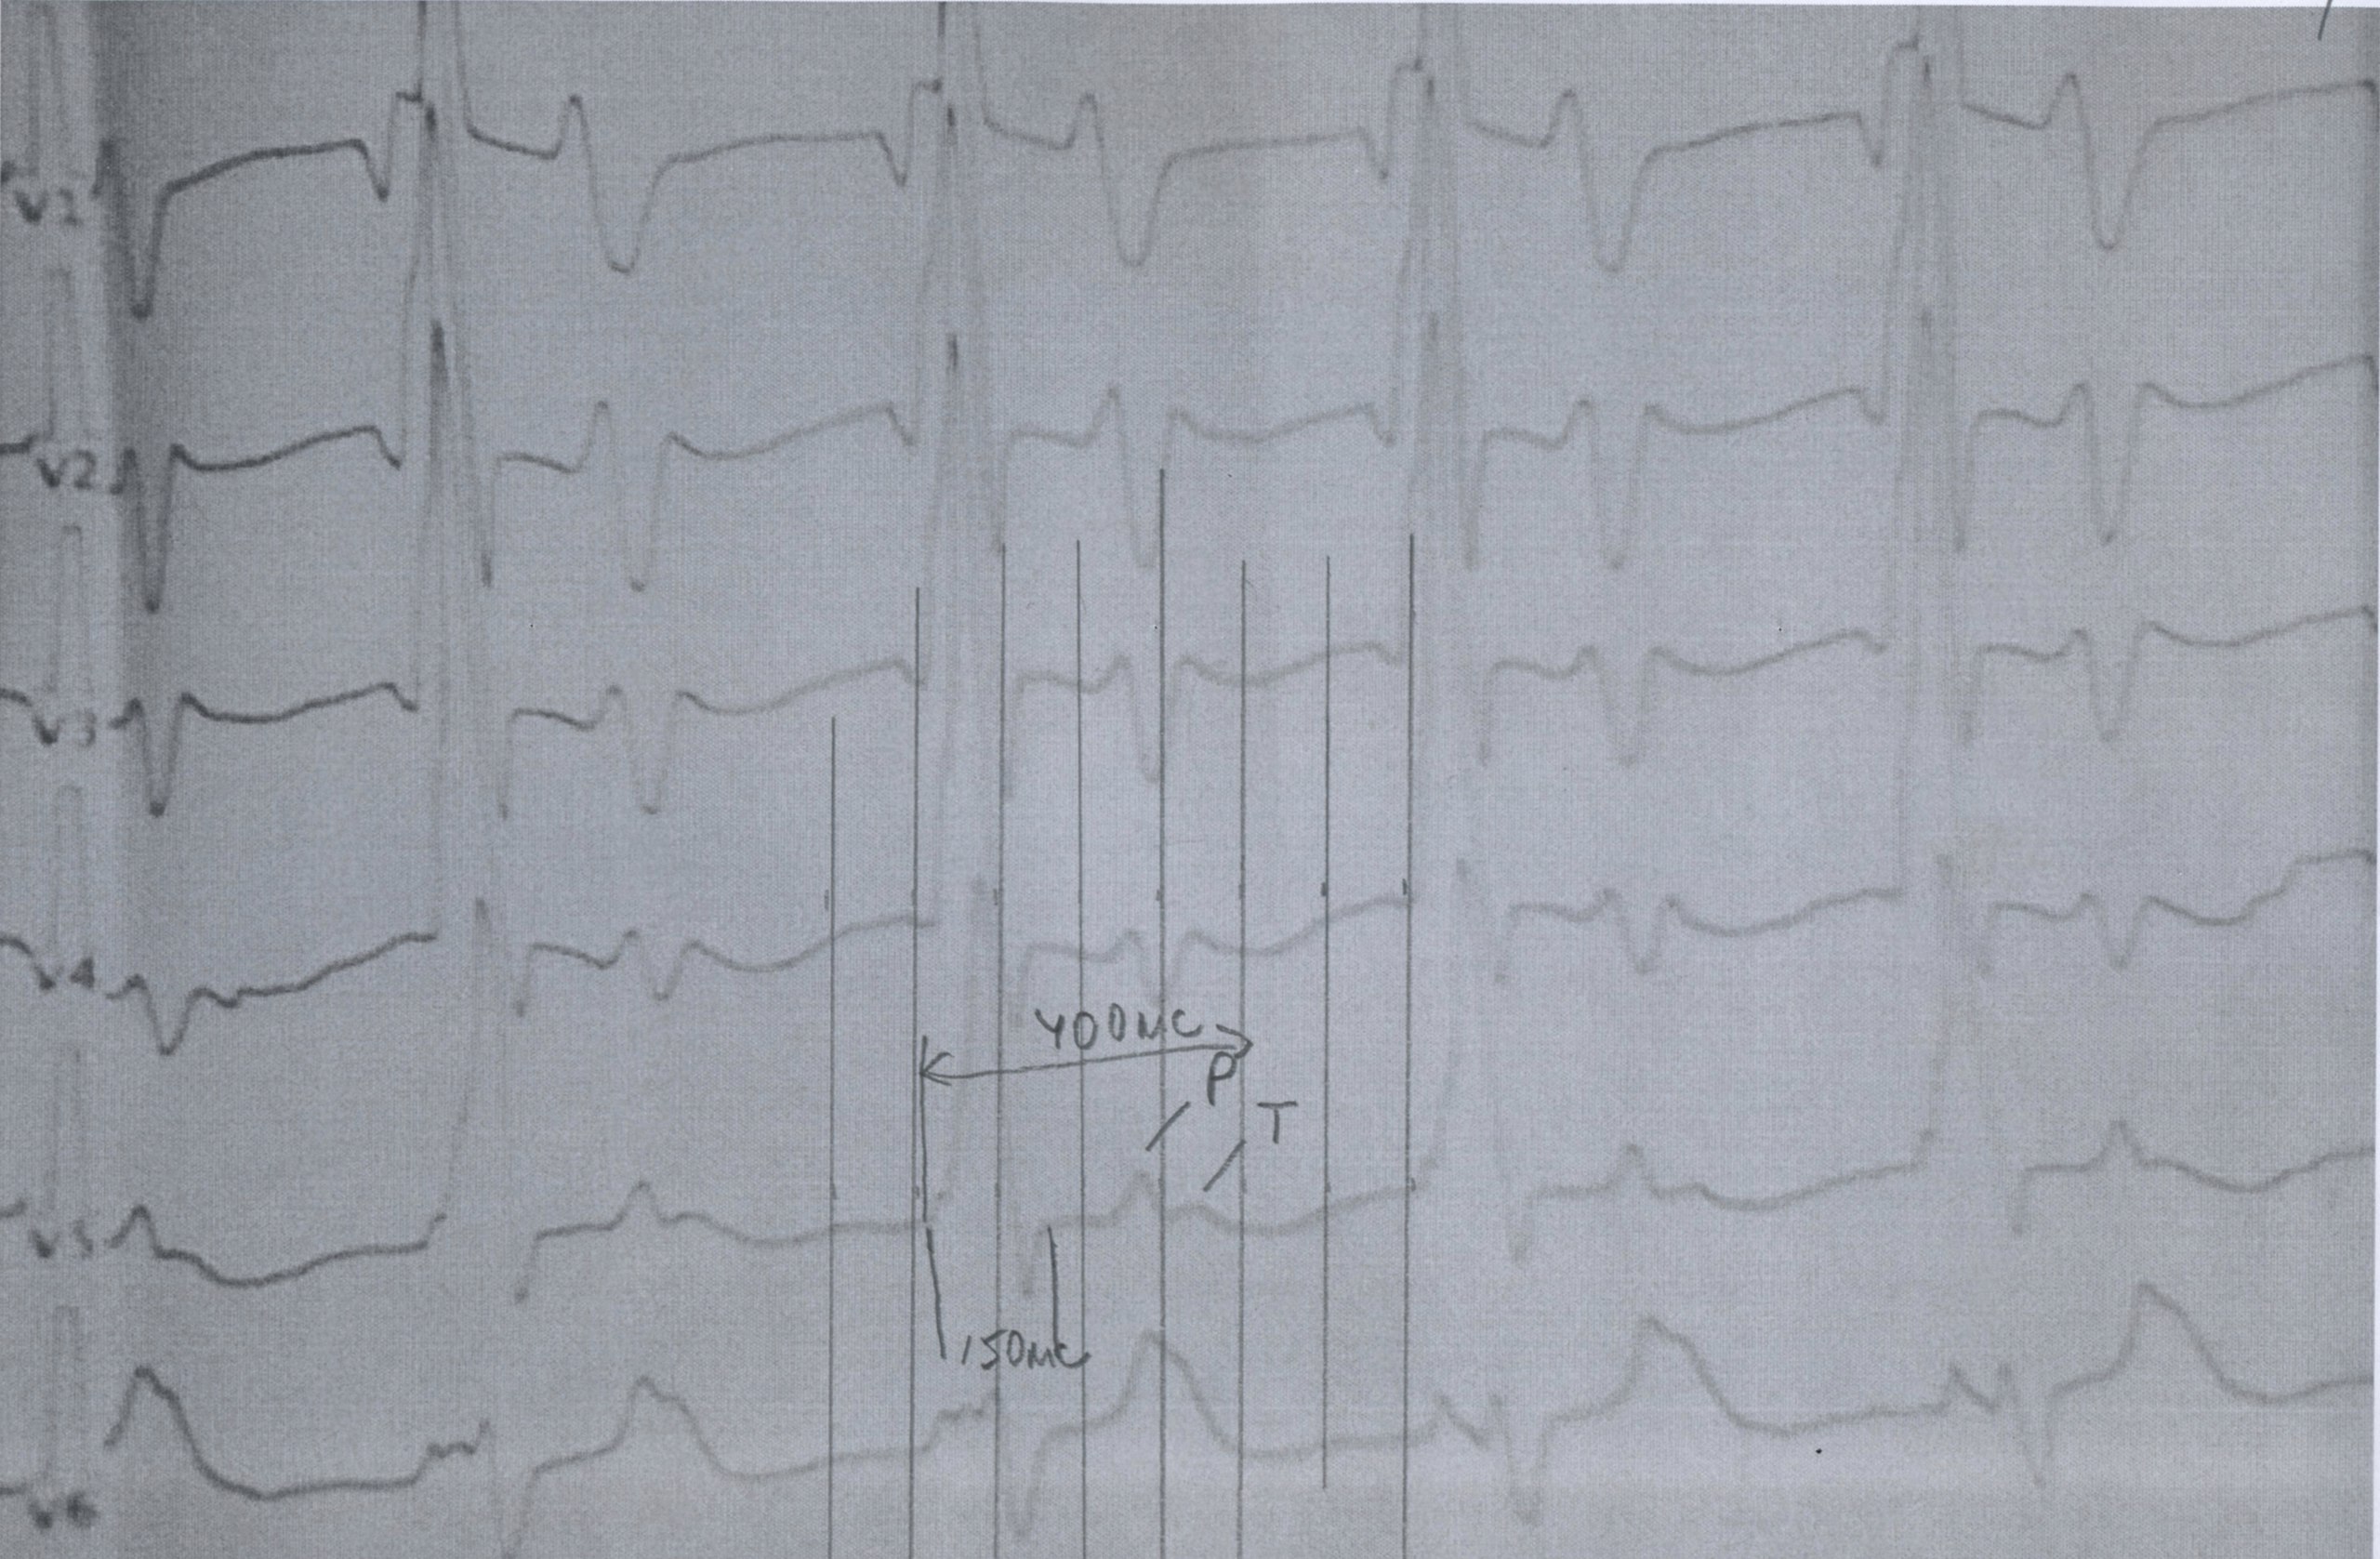

Анамнез - аномальное отхождение магистральных сосудов, сосуды из одного желудочка. Порок не коррегированный

Ритм АВ узла